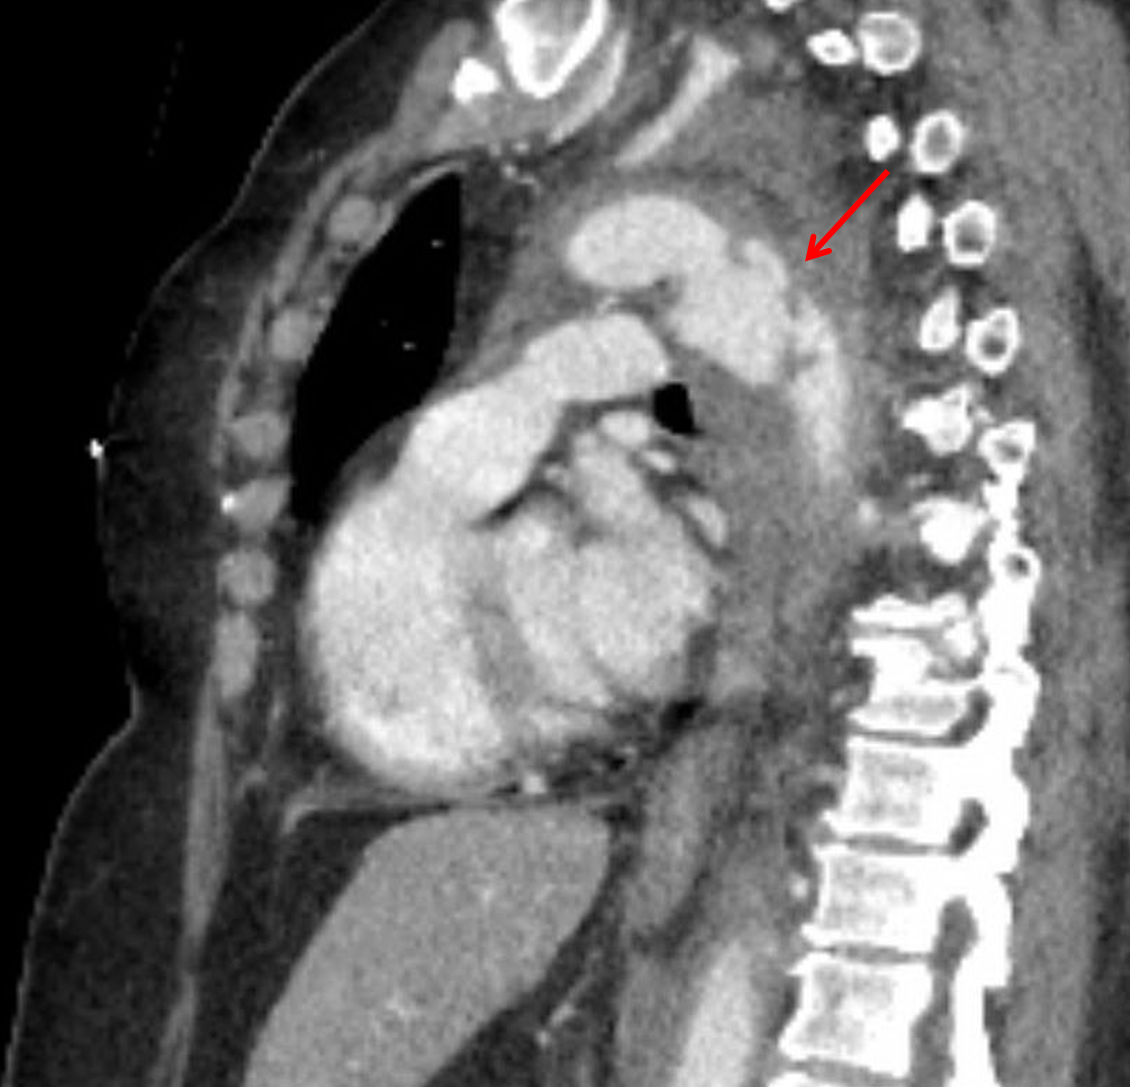

Age: 66

Sex: Female

Indication: Trauma

Sample ReportSevere acute traumatic aortic injury just distal to the origin of the left subclavian artery with external contour irregularity concerning for full-thickness mural tear. Limited evaluation for active bleeding as no delayed images were obtained through the chest, but there is a large surrounding mediastinal hematoma and moderate-sized left hemothorax.

Additional site of aortic injury just below the diaphragmatic hiatus with extension into and occlusion versus near occlusion of the left renal artery. No large surrounding hematoma. Resultant ischemia of the majority of the left kidney.